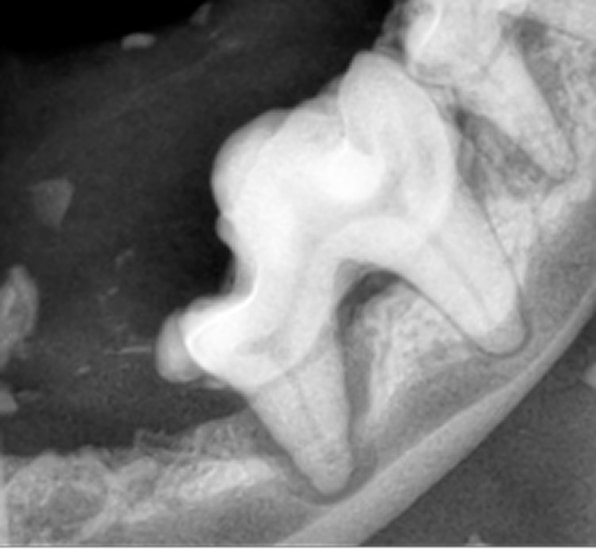

犬の歯周病は、口臭や歯のぐらつきなどから始まり、進行すると歯の痛みや脱落、全身疾患につながるリスクがあります。歯周病はプラークや歯石の蓄積によって引き起こされるもので、これが原因で歯周組織が徐々に破壊されていきます。早期の段階では、炎症や腫れを伴い、犬が口元を気にする仕草が見られることが多いです。しかし、口の痛みがあっても食欲が落ちにくいため、見過ごされやすいので注意が必要です。

治療は内科療法で症状を軽減することはできますが根治は難しく、根本的には全身麻酔下での歯石除去、歯周ポケットのクリーニング、抜歯が必要になることもあります。